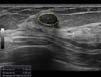

The machine learning algorithm Dr. Luong and her team developed and used in her recent study, published in Echo Research & Practice, was assessed for its performance identifying the indicators of disease present in point-of-care ultrasound (POCUS) images.

The handheld POCUS devices use sound waves to record video footage of heart function at the bedside on miniature machines, instead of through an appointment with a specialist for an echocardiogram.

The research team wanted to know how well their machine learning algorithm measured left ventricular ejection fraction in images captured by both novice and moderately experienced healthcare workers.

Left ventricular ejection fraction is the amount of blood being pumped by the heart within a given time frame – essential information for assessing heart failure and making treatment recommendations.

The machine learning model was previously trained to identify normal and abnormal left ventricular ejection fraction using 2,920 videos from 2,127 patients. While it sifts through video footage, the AI’s assessments are made by video segments, frame by frame, stated Dr. Luong.

For the study, two nurse practitioners with little to no experience using POCUS and seven physicians with moderate POCUS training performed POCUS scans on 138 adult patient volunteers recruited from a heart failure clinic in Vancouver.

The 1,257 videos of the patient scans were analyzed by the research team’s ma-

chine learning algorithm and an expert echocardiographer.

Dr. Luong and her team found a high degree of correlation – around 80 percent similarity between the AI and expert’s estimation of left ventricular ejection fraction for cardiac POCUS images of heart failure patients. The performance of the model was preserved even when accounting for the scanners with lower levels of POCUS experience.